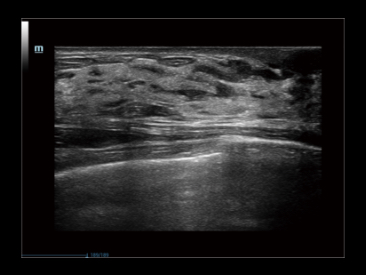

iClear+ Caso: ArticulaciĂłn de hombro